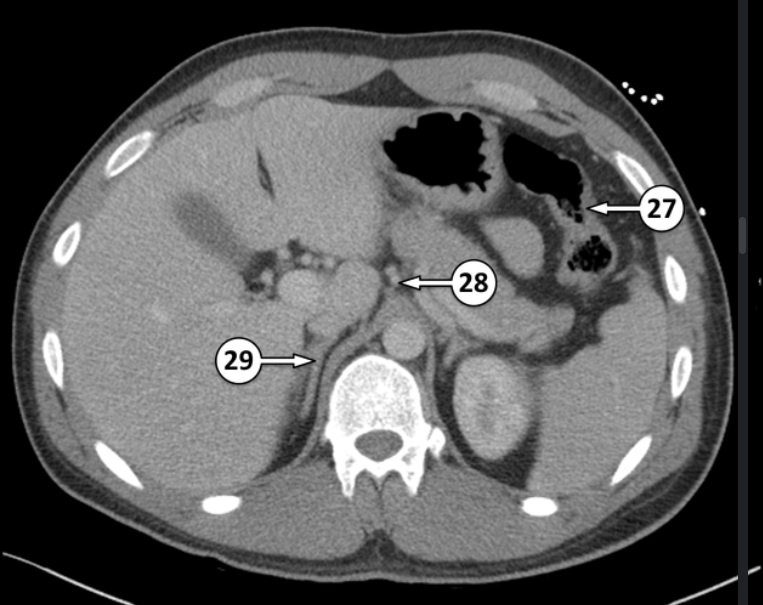

What is 27 and 28?

Splenic flexure

Left gastric artery